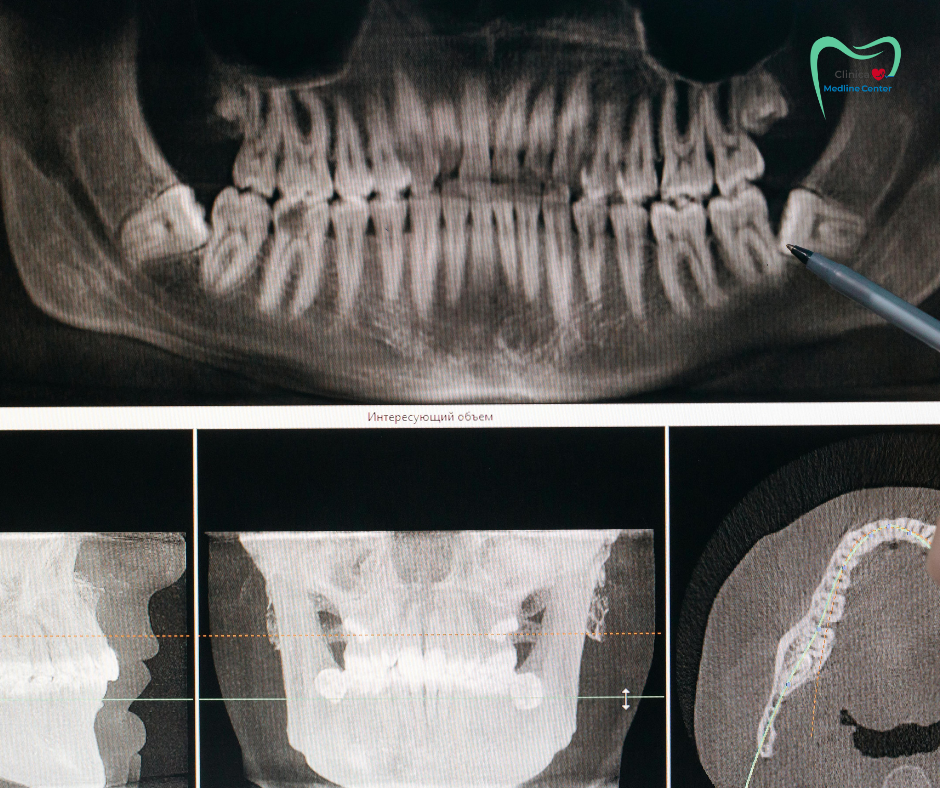

În primă rând, este nevoie de o evaluare clinică și uneori și de o evaluare radiologică (la recomandarea medicului ortodont). Acestea ajută la stabilirea unui diagnostic corect și ulterior la schițarea planului de tratament, situație în care soluțiile vor fi adaptate în funcție de vârsta pacientului, de gradul de severitate al problemei, de eventualele probleme de sănătate/istoric medical și de obiectivele urmărite.